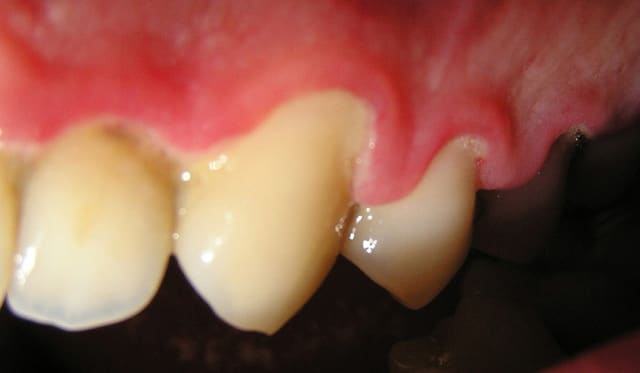

J'ai ressorti les photos prises initialement:

22/06/2005 à 02h01